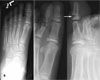

Salter-Harris II Fracture of the Distal Phalanx

A 10-year-old boy stubbed his toe while running upstairs barefoot. He presented with tenderness, swelling, and ecchymosis of the left great toe and bleeding in and around the nail fold (A). Radiographs of the left foot revealed a Salter-Harris II fracture of the distal phalanx (B).

Stubbing injuries to the great toe can cause occult open fracture and subsequent osteomyelitis. Such injuries are most common during the summer when children go barefoot and stub their toes on a shallow ridge, such as a sidewalk crack or tree stump that is cut near ground level.1-3 The stubbing results in forceful hyperflexion of the great toe that causes fracture through the growth plate with flexion deformity.

Bleeding in or around the nail fold, at times in association with laceration proximal to the nail fold, suggests an open fracture. At the root of the nail, the dermis of the skin is attached directly to the periosteum with no intervening subcutaneous tissue. This area is directly above the physis. Any fracture of the physis is likely to extend through the adjacent skin to create an open fracture, with substantial risk of contamination of the wound in children who play barefoot. Osteomyelitis has also been reported in patients with fractures of the distal phalanx of the finger, either occult or with associated fingernail avulsion, who did not receive prophylactic antibiotics.4,5

Treatment of stubbed toe injuries with occult open fractures should include irrigation and debridement, chlorhexidine gluconate soaks, a course of oral antibiotic therapy, and fracture care.